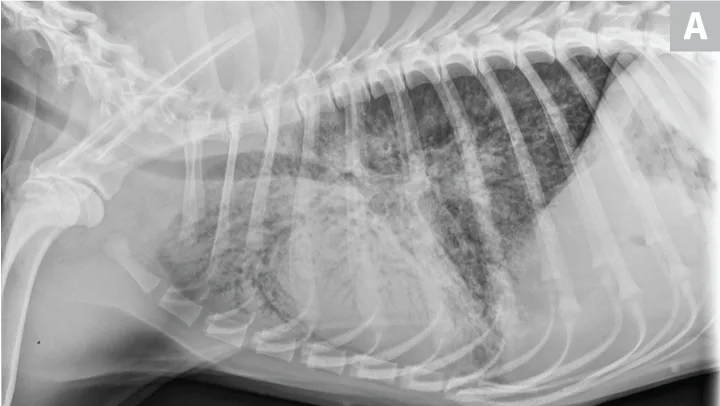

Pulmonary neoplasia may, on occasion, have a more diffuse nature. This is common with pulmonary lymphoma40 and is sometimes seen with carcinoma (author experience). Pulmonary lymphoma can have a rapid clinical course and mimic acute disorders. A diffuse, unstructured interstitial pattern is typically appreciated. Additionally, bronchointerstitial, alveolar, and nodular patterns may be observed (Figure 7).40

FIGURE 7

(A) Pulmonary lymphoma with a diffuse, patchy bronchointerstitial pattern confirmed on bronchoalveolar lavage and peripheral lymph node aspiration. (B) Pulmonary carcinoma with a diffuse, severe bronchointerstitial pattern confirmed on bronchoalveolar lavage and postmortem examination. Note: Pulmonary and hilar lymphadenopathy are not always present.